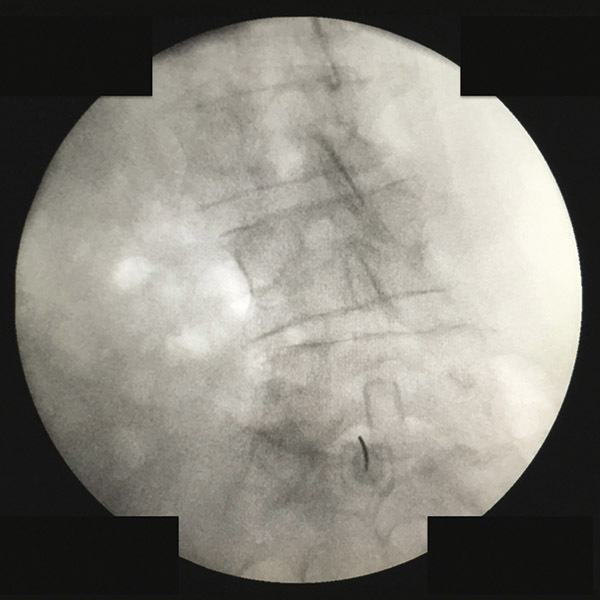

Abord interlamaire L5 sous fluoroscopie

2. Abord interlamaire L5 sous fluoroscopie